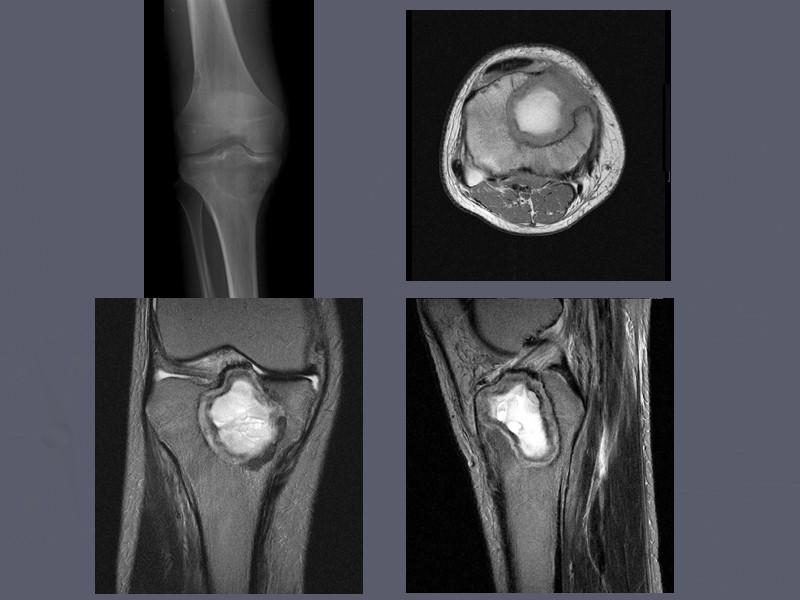

Рентгеновские снимки доброкачественных опухолей костей